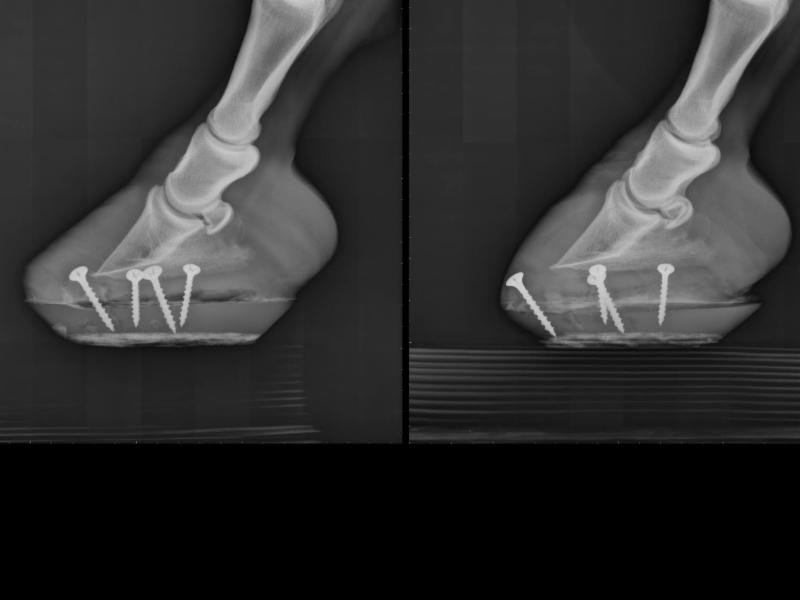

The study echoes our own experience at Dutch Dreamhorses Rehabilitation Center. Below is an example of a laminitis case we recently treated. This pony had a history of laminitis flareups for several years, but this winter it became much worse. When the coffin bone began to rotate, her veterinarian recommended she should be brought to the rehab center to use the Vitafloor® stall unit. She was already in clogs that were screwed on as she couldn’t handle the pain of nailed on shoes. The left x-ray was taken just before Vitafloor® sessions began, and shows a clear example of foundering with some rotation. She then started twice daily Vitafloor® therapy sessions. The right x-ray shows the same foot just under six weeks later. As the radiographs show, the sole growth is impressive. Note how the angles are improved as the farrier was able to take off a large amount of toe due to increased hoof growth, and the sole thickness has increased dramatically. This pony is now back at home having made a complete recovery.